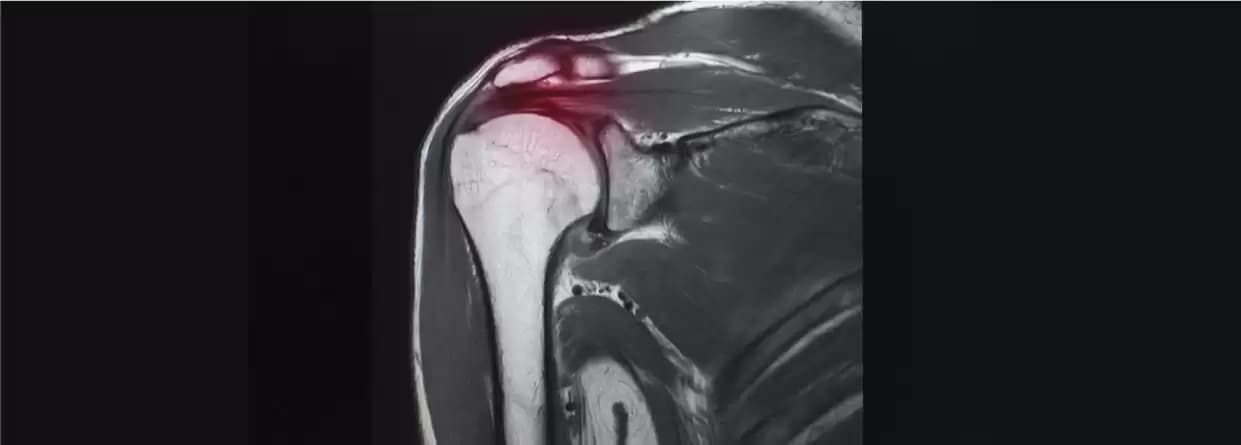

It is very important to get a proper diagnosis of frozen shoulders. Any injury to the shoulder and arthritis can also have frozen shoulder symptoms. Consulting your orthopaedic doctor is the first step to getting the right diagnosis. The orthopaedic doctor will begin by manipulating the affected shoulder. The doctor will order an X-ray for the right diagnosis. Then if the X-ray is also not clear, an MRI may be done. This is usually done by injecting dye into the affected shoulder to see exactly where the problem exists.